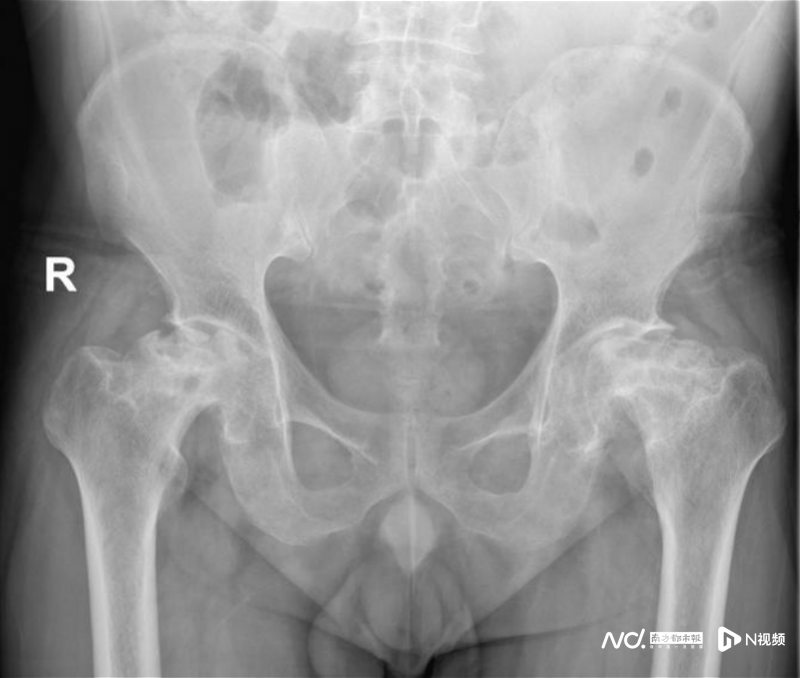

49歲的沈先生6年前被診斷出股骨頭壞死,一直未規(guī)范治療。前不久,因病情加重致行走困難,沈先生到廣州和平骨科醫(yī)院求醫(yī)。醫(yī)生經(jīng)過詳細檢查發(fā)現(xiàn),沈先生雙側(cè)股骨頭缺血性壞死,雙髖關節(jié)退變、半脫位,而發(fā)生這一切的原因與他長期飲酒、長期使用激素有關。

前不久,因病情加重致行走困難,影響日常生活,他才來到廣州和平骨科醫(yī)院骨科就診。經(jīng)過相關檢查后,確診為“雙側(cè)股骨頭缺血性壞死、雙髖關節(jié)退變、雙側(cè)髖關節(jié)半脫位”,需要進行雙側(cè)人工全髖關節(jié)置換。

術前影像檢查,患者的雙側(cè)股骨頭均已嚴重壞死。